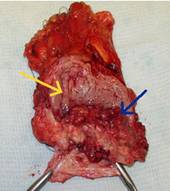

Мышечно-инвазивный рак мочевого пузыря (нормальная слизистая - желтая стрелка, опухоль - синяя стрелка)